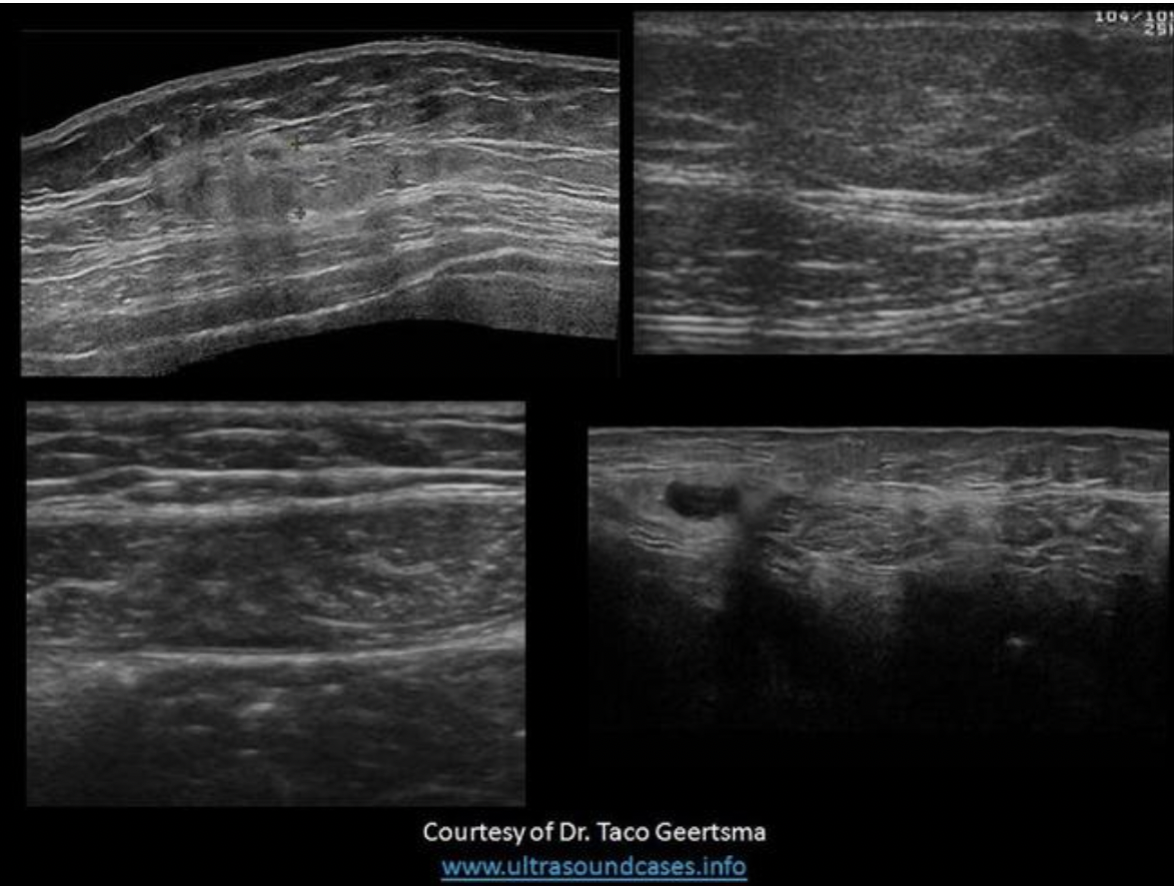

Find the rectus sheath hematoma

Top left is a benign mass with lobulated borders and the top right is a lipoma. Both are located in the subcutaneous tissues/fat between the skin and the anterior rectus sheath. The lipoma has smooth borders and an echogenicity similar to the surrounding fat.

The bottom right image demonstrates a spigelian hernia, between the right rectus abdominis and right oblique muscles.

The bottom left image demonstrates a hematoma in the rectus abdominis muscle, between the anterior and posterior rectus sheaths.

Find the lipoma

The top two images demonstrate solid masses that are superficial to the rectus abdominis muscle. Top left is a benign mass with lobulated borders and the top right is a lipoma. Both are located in the subcutaneous tissues/fat. The lipoma has smooth borders and an echogenicity similar to the surrounding fat.